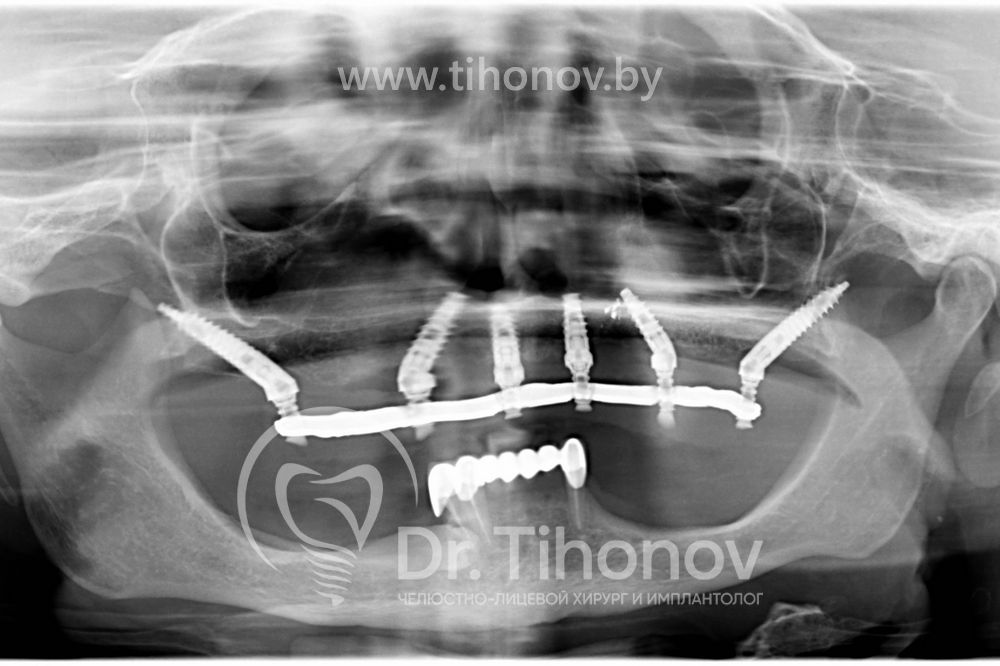

После изучения данных 3D-исследования челюстей и клинической ситуации в полости рта на очной консультации было принято решение о протезировании зубов на верхней челюсти при помощи методики All-on-6 (все на 6-ти). В день операции на верхней челюсти были удалены несостоятельные протезы и разрушенные корни зубов, установлены 6 имплантатов, в течение 4 дней был изготовлен и фиксирован несъемный металлопластмассовый эстетичный протез на верхнюю челюсть. Использование методики протезирования All-on-6 (все на 6-ти) в данном клиническом случае позволило полностью удовлетворить потребности пациентки.